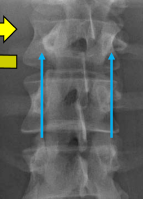

Q what is the name of this measurement? and what is the average + range?

A: Interpediculate distance

assesses the distance between the medial aspects of the pedicles. The range is 1.4-2.0 cm.